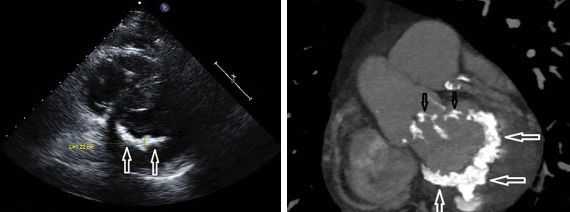

Другой важный инструментальный метод диагностики — эхокардиография (Эхо-КГ) . Эхо-КГ — это безболезненное ультразвуковое исследование, которое позволяет исследовать работу сердца в реальном времени. Эхокардиография покажет уменьшение эластичности клапана, его повреждение, размер отверстия митрального клапана и расстояние между его створками. Также при исследовании можно увидеть разрыв папиллярной мышцы и провисание клапанных створок в полость левого предсердия [4] [8] [9] .

Эхокардиография позволяет определиться с этиологией митральной недостаточности, оценить ее тяжесть, наличие осложнений. С помощью допплерэхокардиографии выявляется регургитация через митральное отверстие, определяется ее интенсивность и величина, что в совокупности позволяет судить о степени митральной недостаточности. При наличии фибрилляции предсердий прибегают к чреспищеводной ЭхоКГ с целью выявления тромбов в левом предсердии. Для оценки тяжести митральной недостаточности применяется зондирование полостей сердца и левая вентрикулография.